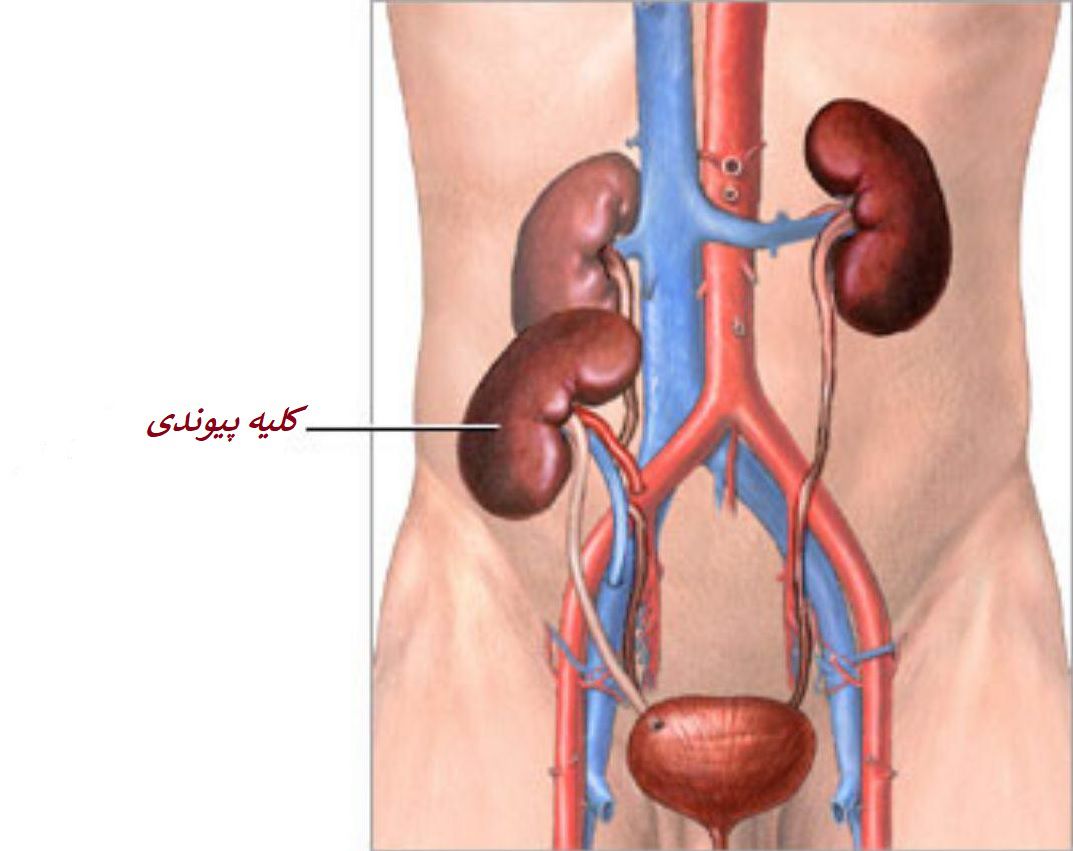

عکس کلیه در بدن. اگر پشت یا پهلوی شما آسیب ببیند مثل برخورد ضربه ممکن است فکر کنید که کلیه هایتان درد می کنند. مقدار و نسبت ترکیب این اخلاط در بدن هر شخصی و در اندامهای. کلیه گ رده ها1 از اندام های درونی بدن انسان به صورت یک جفت عضو لوبیایی شکل در طرفین ستون فقرات روی جدار پشتی شکم و بیرون از حفره صفاق قرار دارند. ک لیه ق لوه میز یا گ رده یکی از اندام های درونی بدن انسان و برخی دیگر از جانداران است.

کلسیم و فسفر که برای تشکلی استخوان لازمند کمک می کنند مواد. کلیه ها با تولید ادارد در دفع مواد زاید تعادل الکترولیتی تنظیم هورمونی تنظیم فشار خون و هوموستازگلوکز نقش دارند. آناتومی کلیه انسان در بدن انسان به این شکل است که کلیه ها دو عضو لوبیایی شکل در دستگاه ادراری بوده و به دفع مواد زائد به صورت ادرار کمک می کنند. یکی از مهم ترین وظایفی که کلیه ها در بدن بر عهده دارند پاک کردن و تصفیه خون از زباله هاست.